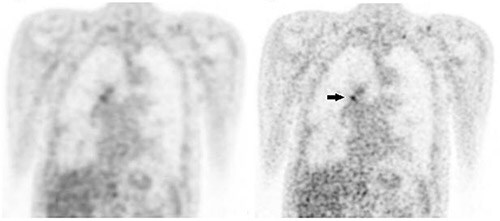

Figure 2: F18-FDG Pet images with standard voxel reconstruction (A) and small voxel reconstruction (B). The SUVmax of the lesion in the right hilar region (volume 0.50 mL) with a SUVmax of 3.0 using the standard voxel reconstruction, increased by 45% to 4.4 on the small voxel reconstruction (black arrow). The SNRmax increased by 77% (from 9.8 to 13.3).